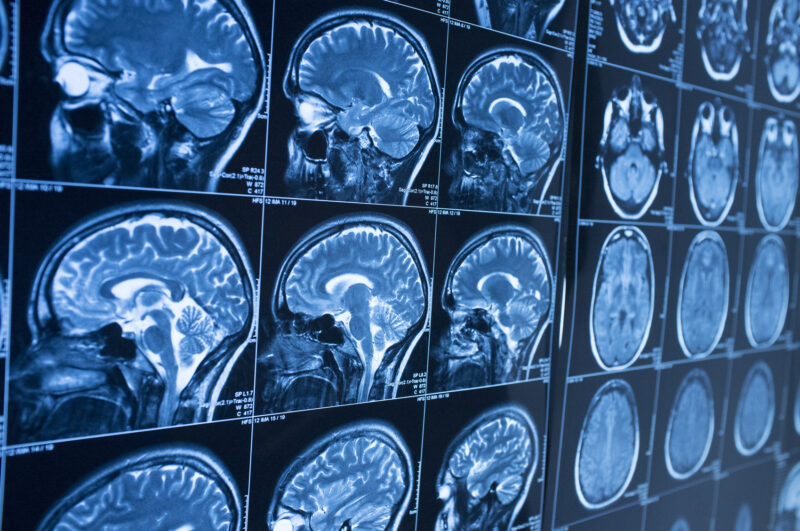

There are two primary types of brain injuries:

- Traumatic brain injuries (TBIs): when the brain is injured due to external force or trauma, which may include both open and closed wounds sustained during falls, assaults, traffic accidents, etc.

- Non-traumatic brain injuries (NTBIs): when the brain is injured because of internal factors, which may include oxygen deprivation, toxic exposure, etc.

TBIs and NTBIs fall under the umbrella of “acquired brain injuries” (ABIs), a term that covers all head injuries that are not hereditary, degenerative, or present or induced at birth.

Treatment and Recovery

Unfortunately, the brain cannot regenerate destroyed brain cells, so recovery focuses on rewiring different parts of the brain to take over the functions of the dead cells. As such, many individuals with these injuries are able to recover to at least some extent. It is important to note that the sooner a person obtains medical treatment for an ABI, the more effective treatment will be. For this reason, it is crucial to know the symptoms of ABIs.